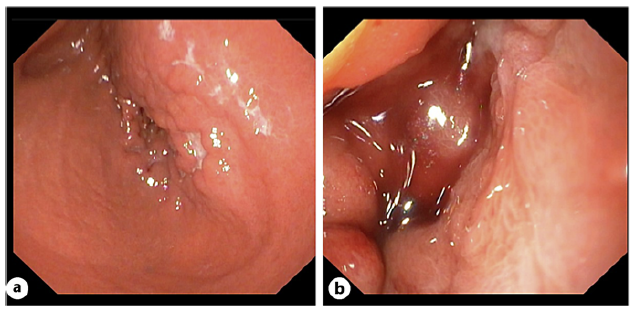

A previously healthy 22-year-old male presented to our hospital with a 2-month history of heartburn, postprandial vomiting, and significant weight loss. Physical examination revealed a soft, non-tender abdomen. Laboratory tests showed microcytic anemia (Hb 11.3 g/dL, MCV 66 fL) and thrombocytosis (544 × 109/L), with normal amylase and lipase levels. Upper endoscopy identified antral ulcerations and a severely stenotic pylorus (Fig. 1), preventing further scope advancement. A subsequent abdominal computed tomography scan revealed marked gastric distension, a significant reduction in the caliber of the second portion of the duodenum, and abnormal projections of the pancreatic head wrapping the descending part of the duodenum (Fig. 2).